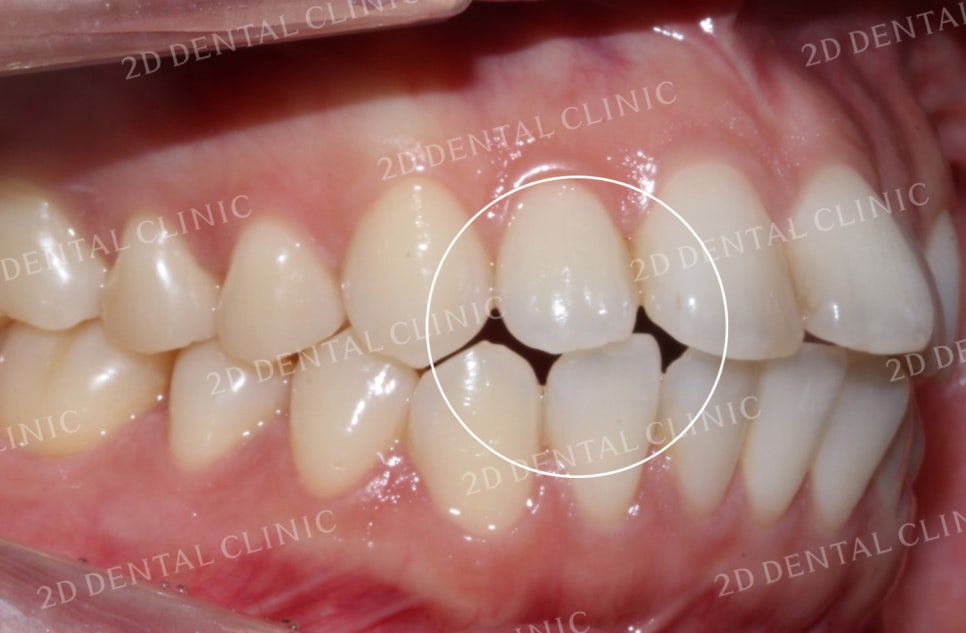

좌우의 안모 사진입니다.

표시된 부분에서 완전히 맞물리지 못한

치아 사이의 틈이 발견되고 있네요.

이러한 교합면 사이의 빈 공간은

음식물 섭취 시 불편을 유발하는 원인 중 하나입니다.